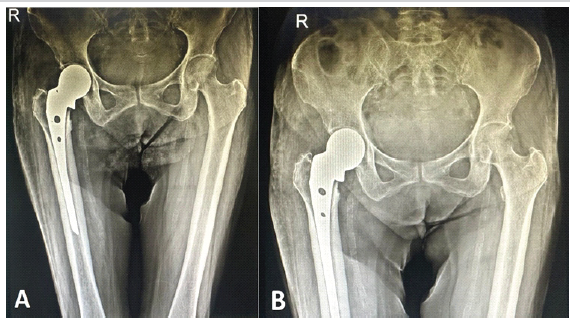

The patient was followed regularly during the first 6 months after surgery (Fig. 3).

Figure 3: (a) Immediate post-operative radiograph, (b) radiograph at 6 months of follow-up.